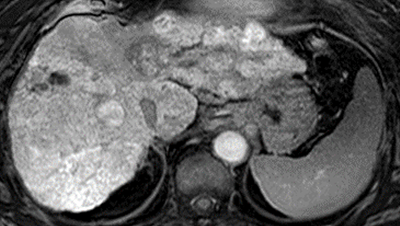

肝動脈化学塞栓療法と薬剤2種の併用で肝細胞がんへの治療効果が向上 レンバチニブとペムブロリズマブ併用による肝細胞がんの完治に期待

学校法人近畿大学

2025年1月9日 08:30

肝細胞がん免疫療法の効果を予測する画像バイオマーカーを発見 免疫療法の効果がない患者に対するMRI診断の有効性を証明

2021年8月19日 21:00